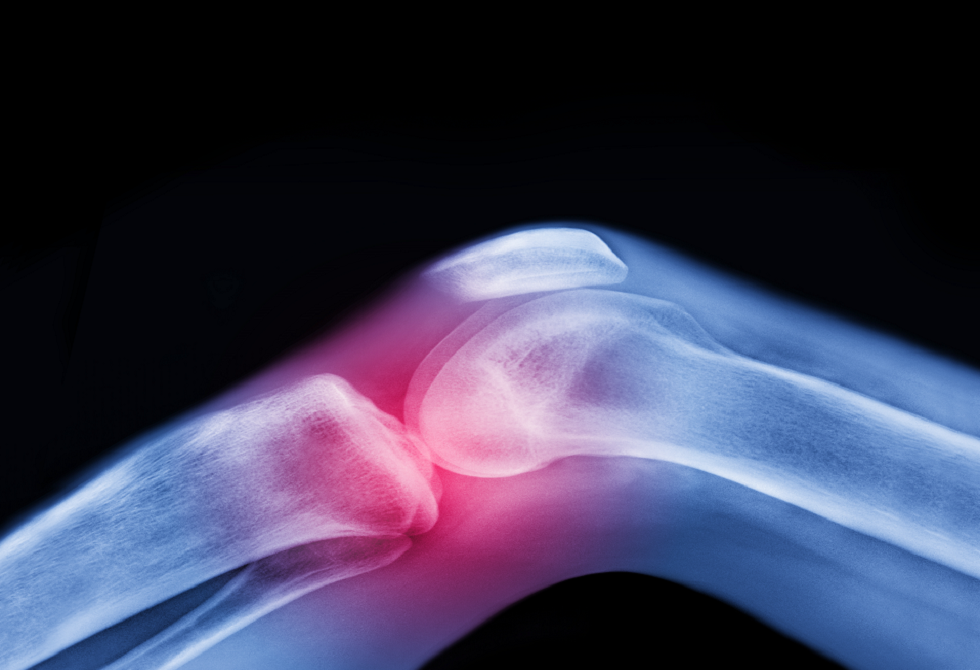

تعتبر آلام المفاصل وتيبّس الركبتين وأوجاع الوركين من الشكاوى الشائعة بين كبار السن، وغالبا ما يُقبل بها كجزء طبيعي من أعراض الشيخوخة.

لكن الواقع الطبي يوضح أن هذا ليس مصيرا حتميا، فالفصال العظمي أكثر أمراض المفاصل شيوعا في العالم يمكن الوقاية منه وعلاجه بطرق غير دوائية فعّالة للغاية.

ويرى الخبراء أن أفضل علاج للفصال العظمي لا يوجد في علب الأدوية أو غرف العمليات، بل في الحركة المنتظمة والتمارين الرياضية. ومع ذلك، تظهر الدراسات أن القليل فقط من المرضى يتلقون الإرشاد المناسب لاستخدام هذا العلاج الفعال.

وتشير أبحاث أُجريت في أنظمة الرعاية الصحية في إيرلندا والمملكة المتحدة والنرويج والولايات المتحدة إلى نمط مقلق: أقل من نصف المصابين بالفصال العظمي يُحالون إلى العلاج الطبيعي أو التمارين الرياضية من قبل أطباء الرعاية الأولية. وفي الوقت نفسه، يحصل أكثر من 60% من هؤلاء المرضى على علاجات لا تتوافق مع الإرشادات الطبية، بينما يُحال نحو 40% إلى الجراحة قبل تجربة الخيارات غير الجراحية.

ولا يعتبر الفصال العظمي مجرد تآكل ميكانيكي للمفصل، بل مرضاً يؤثر على جميع مكوناته: السائل الزلالي والغضروف والعظم والأربطة والعضلات المحيطة، وحتى الأعصاب التي تدعم الحركة. وتستهدف الحركة المنتظمة جميع هذه العناصر، وتحافظ على صحة المفصل…..